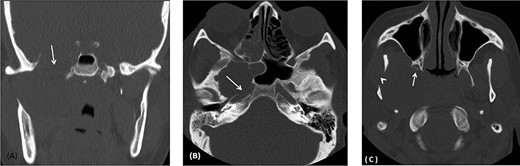

(A) Image-guided tumor removal from petrous carotid artery. (B) Image-guided intraoperative picture status post-complete tumor removal from trigeminal and middle cranial fossa.

The patient underwent an image-guided endonasal endoscopic tumor removal starting by endoscopic medial and posterior walls maxillectomies to control the tumor removal from the lateral sphenoid sinus and the infratemporal fossa after cauterization of the maxillary artery and sphenopalatine artery branches feeding the tumor. The tumor was dissected and removed from the cavernous (Fig. 3A) and petrous carotid artery in the middle cranial fossa (Fig. 3B). The middle cranial fossa’s dura was intact during the tumor removal (Fig. 3C). All the steps of tumor removal were controlled and monitored under image-guided navigation for accurate localization of tumor removal and avoidance of violation to the middle cranial fossa’s dura, or the brain, and the internal carotid artery in its cavernous and petrous segments (Fig. 4a and b).